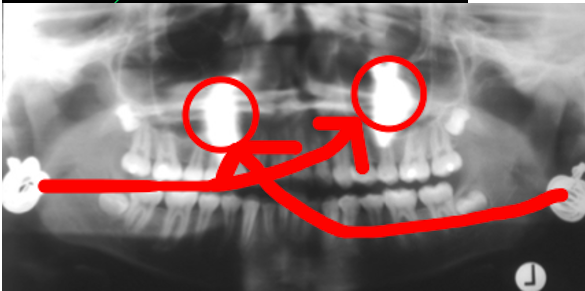

What is a ghost image on an OPG?

- Object between x-ray source and centre of rotation

- Usually outside of focal trough: appears blurred and magnified

- Appears on opposite side of image (L↔R) and higher on the image (due to upward beam) than their anatomical location

- Mandibular ramus, hyoid bone, cervical spine, earrings, etc.